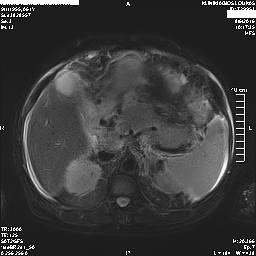

Στα πλαίσια διερεύνησης του πρωτοεμφανιζόμενου διαβήτη, υποβλήθηκε σε μαγνητική τομογραφία άνω κοιλίας (MRI/MRCP) που ανέδειξε μια συμπαγή μάζα στην κεφαλή του παγκρέατος, διαμέτρου περίπου 2εκ και μεγάλη διάταση του παγκρεατικού πόρου.

ΜRCP: διάταση παγκρεατικού πόρου